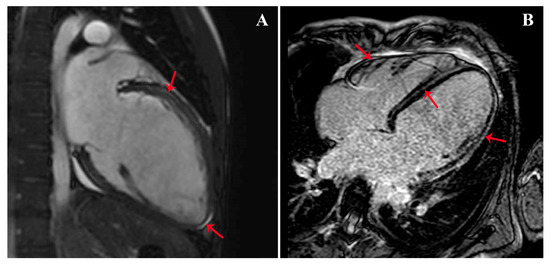

A Young Patient Presenting with Dilated Cardiomyopathy and Renal Infarction during Treatment with Isotretinoin: Mere Coincidence or Serious Side Effect of a Drug Commonly Used in Adolescence?

Isotretinoin or 13-cis-retinoic acid (RA) is one of the most effective and widely used drugs for the treatment of severe acne vulgaris. Despite being deemed safe, no definite consensus has been reached on the cardiovascular risk of RA derivatives. We report a case [...] Read more.

Isotretinoin or 13-cis-retinoic acid (RA) is one of the most effective and widely used drugs for the treatment of severe acne vulgaris. Despite being deemed safe, no definite consensus has been reached on the cardiovascular risk of RA derivatives. We report a case of heart failure due to dilated cardiomyopathy (DCM) and concomitant renal infarction occurring after 5 months of isotretinoin use in a previously healthy 18-year-old male. The patient, with a history of acne vulgaris, presented to our emergency department with left iliac fossa pain and effort dyspnea. A trans-thoracic echocardiogram showed DCM and severely reduced left ventricle ejection fraction (LVEF: 29%). During hospitalization, a total body computed tomography (CT) showed an ischemic lesion in the left kidney. Ischemic, autoimmune, infective, and heritable causes of DCM were ruled out. Cardiac magnetic resonance (CMR) evidenced LV circumferential mid-wall late gadolinium enhancement. Heart failure therapy was promptly started and up-titrated, but only poor LVEF improvement was detected overtime. Our case aims to raise awareness on rare life-threatening cardiovascular events possibly associated with isotretinoin use. To the best of our knowledge, this is the first described case of renal thromboembolism and severe DCM leading to implantable cardioverter-defibrillator (ICD) implantation occurring during isotretinoin treatment. Full article